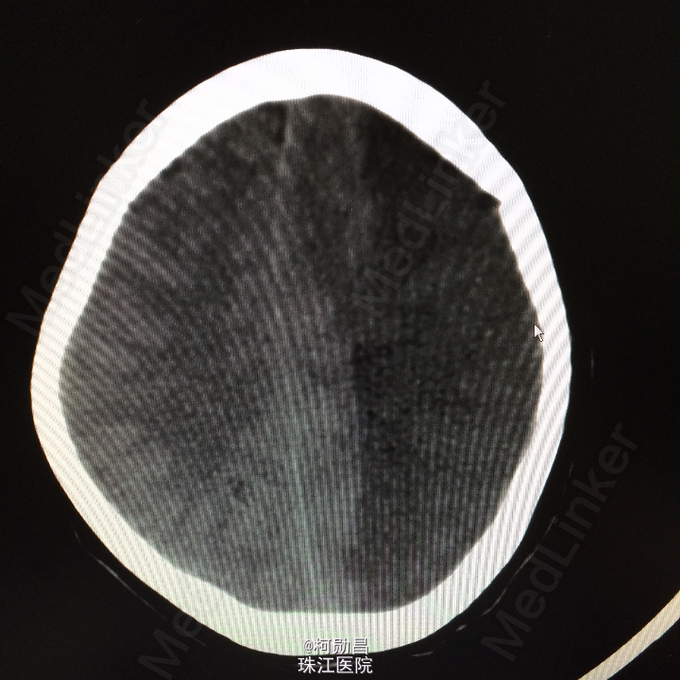

查体:神志呈昏睡状态,言语不能,精神差,双侧瞳孔不等大,左侧3mm,对光反射消失;右侧瞳孔2,mm,对光反射灵敏,右侧肢体肌力0级,左侧肢体肌力5级,右侧肢体肌张力减低,余未见异常。 辅助检查:左侧大脑半球累计岛叶、基底节区(以颞顶叶为主)大片状低密度影,考虑脑梗塞;中线结构明显右移。